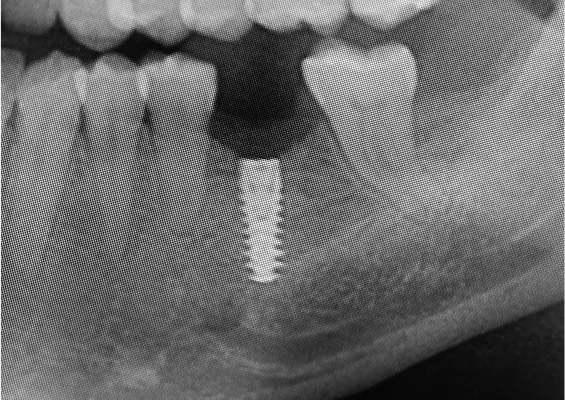

ZABIEGI REGENERACJI KOSTNEJ WOKÓŁ WSZCZEPIANYCH IMPLANTÓW

Sterowana regeneracja kości GBR przy użyciu biomateriałów oraz membran zaporowych. Procedury te są stosowane w sytuacji niedostatecznej ilości kości, skutkującej odsłonięciem gwintu, podczas gdy wszczepiamy implanty stomatolo-giczne lub też jako zabiegi poprzedzające ich wprowadzenie.

Regeneracja kostna to odbudowa kostna przy użyciu odpowiednich technik/procedur oraz materiałów kościotwórczych. Rozwój chirurgii stomatologicznej i szczękowo-twarzowej pozwolił na opracowanie procedur zabiegowych dla regeneracji kostnej u osób, u których doszło do jej zaniku, deformacji lub uszkodzenia. Dzięki nim możliwe staje się zastosowanie implantów stomatologicznych u znacznie większej grupy pacjentów. Ocenia się, iż obecnie regeneracja kości staje się niezbędna w ponad 50% przypadków wszystkich zabiegów implantacji, gdyż warunkiem wszczepienia implantu i osiągnięcia pełnego sukcesu jest odpowiednia ilość kości. Niedostateczna ilość kości ogranicza lub uniemożliwia leczenie implantologiczne.

Przy zabiegu wszczepienia implantu nie zawsze niezbędna jest odbudowa kostna okolicy implantowanej. W sytuacji istnienia prawidłowej objętości kości we wszystkich wymiarach implantujemy bez odbudowy kostnej. Przy niedostatku kości w jednym z wymiarów warunkiem prawidłowego osadzenia i wgojenia implantu jest regeneracja kostna. Ma ona wpływ zarówno na względy biologiczne, czyli prawidłowe wgajanie się implantu, jak i względy funkcjonalne – brak retencji pokarmów pod prawidłowo uformowanymi koronami. Istotne dla pacjenta są również względy estetyczne, które osiąga się poprzez anatomiczne odtworzenie kształtu dziąsła rozpiętego nad odbudowaną kością, dające prawidłowe wyłonienie korony protetycznej odtwarzanego zęba. Uwzględnienie odtworzenia zarówno kości, dziąsła, jak i koron zębów daje w pełni estetyczne i funkcjonalne efekty, które najlepiej imitują własne uzębienie.